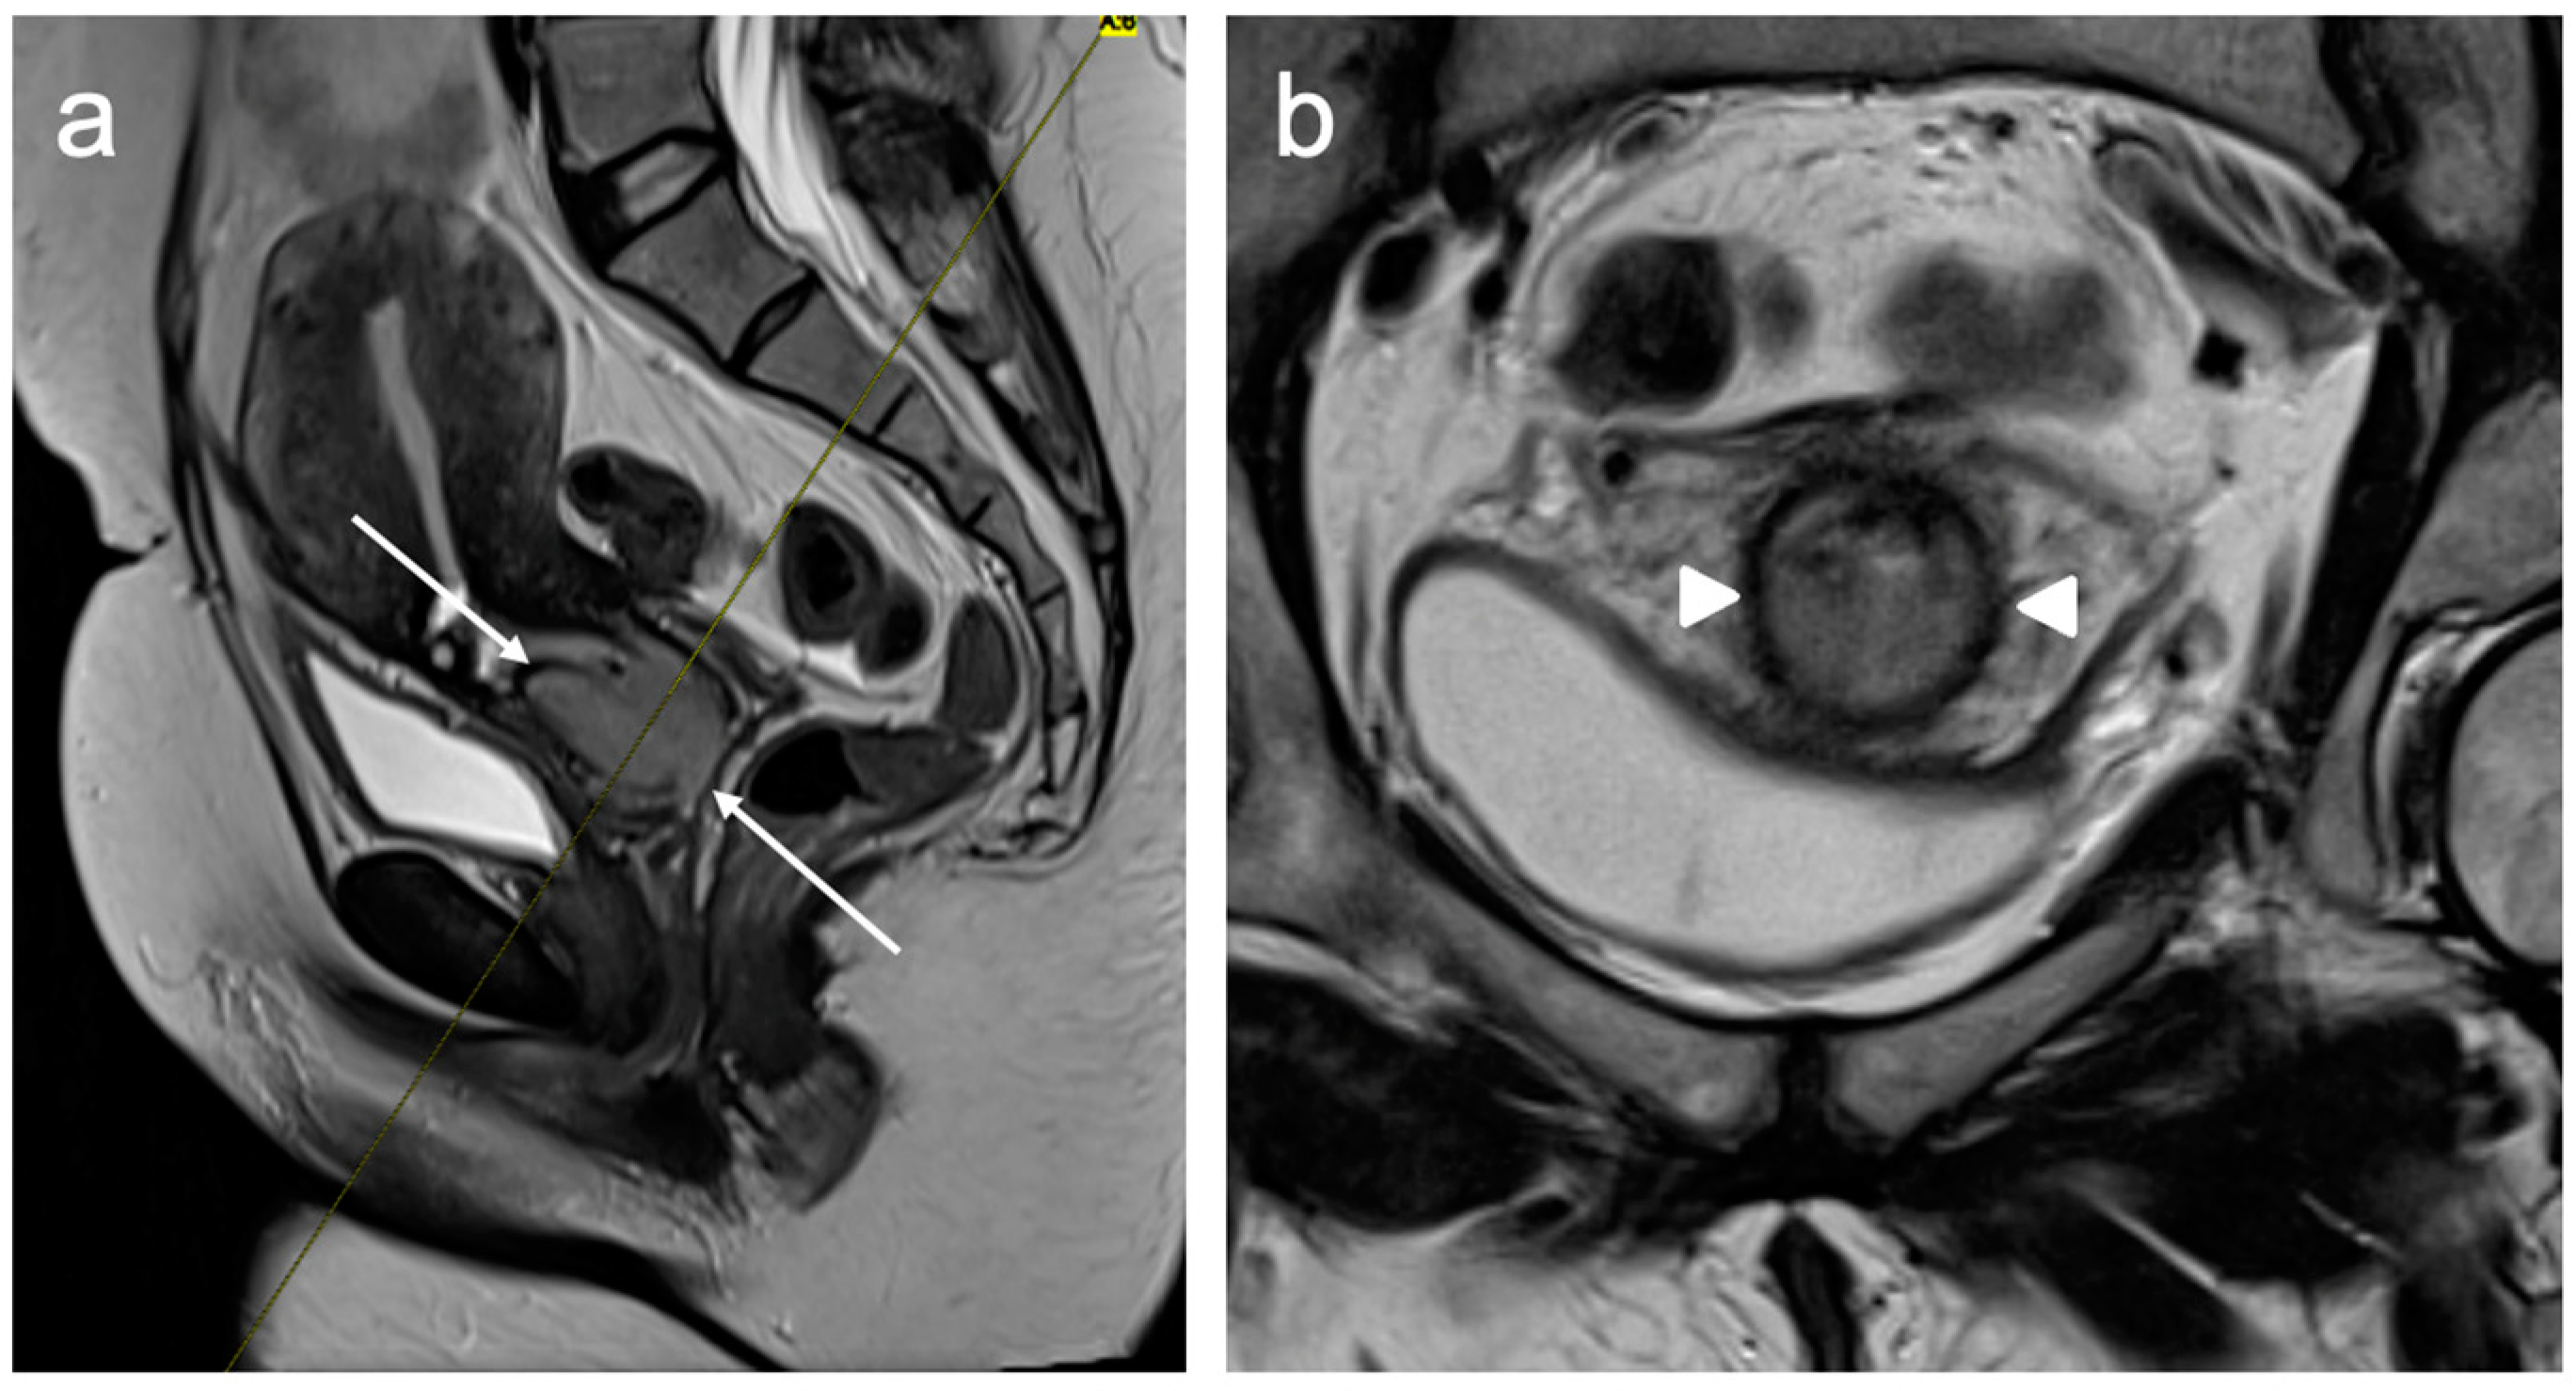

- McEvoy, S.H.; Nougaret, S.; Abu-Rustum, N.R.; Vargas, H.A.; Sadowski, E.A.; Menias, C.O.; Shitano, F.; Fujii, S.; Sosa, R.E.; Escalon, J.G.; et al. Fertility-sparing for young patients with gynecologic cancer: How MRI can guide patient selection prior to conservative management. Abdom. Radiol. 2017, 42, 2488–2512, Erratum in Abdom. Radiol. 2017, 42, 2966–2973. [Google Scholar]

- Halaska, M.; Robova, H.; Pluta, M.; Rob, L. The role of trachelectomy in cervical cancer. Ecancermedicalscience 2015, 9, 506. [Google Scholar] [CrossRef]

- Rockall, A.G.; Qureshi, M.; Papadopoulou, I.; Saso, S.; Butterfield, N.; Thomassin-Naggara, I.; Farthing, A.; Smith, J.R.; Bharwani, N. Role of Imaging in Fertility-sparing Treatment of Gynecologic Malignancies. Radiographics 2016, 36, 2214–2233. [Google Scholar] [CrossRef] [PubMed]

- Noël, P.; Dubé, M.; Plante, M.; St-Laurent, G. Early cervical carcinoma and fertility-sparing treatment options: MR imaging as a tool in patient selection and a follow-up modality. Radiographics 2014, 34, 1099–1119. [Google Scholar] [CrossRef] [PubMed]